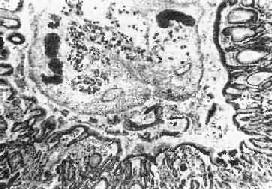

膽道華支睪吸蟲病病理圖在流行區,由於人們普遍對膽道華支睪吸蟲病有所認識,根據臨床表現等很容易確診但在非流行區易導致誤診依據流行病學資料、臨床症狀和體徵、結合實驗室檢查及影像學檢查可明確診斷。

被成蟲寄生的肝膽管,其病變程度與感染華支睪吸蟲的數量多少和感染時間長短有密切關係。如感染的蟲數僅10餘條至幾十條,則肝臟與膽管多無肉眼病變,如寄生蟲數超過100條甚至數千條時,由於蟲體充滿肝內外膽管、膽囊及胰管,引起膽道梗阻,並發膽管炎、肝膿腫、胰腺炎等。華支睪吸蟲病變主要發生在肝內小膽管,因蟲體機械性阻塞和代謝產物的毒性作用,造成膽汁淤積,膽管呈囊狀或圓柱狀擴張,以左葉邊緣部分為著,膽管上皮細胞有脫落和增生膽管壁因結締組織增生而增厚,並有大量腺體增生、淋巴細胞及粒細胞浸潤等現象;鄰近的肝細胞有脂肪變性萎縮和壞死現象,最終導致膽汁性肝硬化。死亡的華支睪吸蟲屍體、蟲卵及脫落的膽管上皮可成為結石形成的核心,誘發肝膽管結石,有報導認為此病與膽管細胞癌有密切關係。